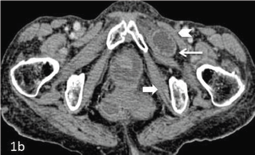

Figure 1b: Axial sections at a caudal level show the incarcerated segment of the herniated loop in the upper thigh anteriorly. The pectineus muscle is seen anterior to the herniated bowel (arrow head) and the obturatorinternus muscle is seen posteriorly (bold white arrow).

An 83 year old lady presented with complaints of acute pain in abdomen and left anterior thigh with non-passage of stools and flatus for the past two days. She had previous history of ischemic heart disease for which she had undergone coronary stenting and pulmonary tuberculosis for which she had completed antitubercular treatment. There was no past history of any abdominal surgery. On examination, she had a thin built with a BMI of 17. At presentation she was dehydrated and pale. Her abdomen was distended, mildly tender with exaggerated bowel sounds. The hernial orifices were clear and rectal and vaginal examinations were unremarkable. No mass was felt at the site of pain in the left anterior thigh. She was resuscitated and underwent an abdominal radiograph that showed multiple air fluid levels and dilated small bowel loops suggestive of mechanical small bowel obstruction. Subsequently, CECT of abdomen was performed which showed dilatation of the small bowel loops (measuring approximately 3-3.5 cm in caliber) with multiple internal air fluid levels. There was herniation of a mid ileal loop for a length of approximately 2.3 cm through the left obturator foramen and was lying in the anterior thigh between the pectineus and obturatorexternus muscles (Figure 1 & 2). The bowel wallshowed normal CT morphology with no features to suggest infarction.